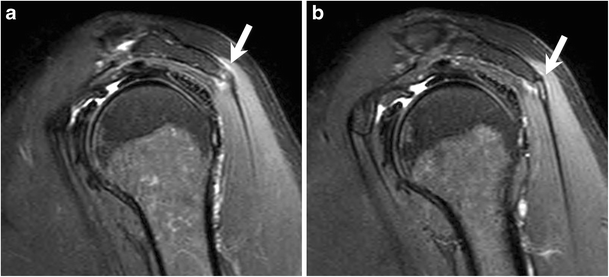

Posterior shoulder enthesitis picture This image illustrates posterior shoulder enthesitis.

The acromial origin of the deltoid is a target structure of ankylosing spondylitis and related spondyloarthritis, which are often overlooked and underdiagnosed as causes of posterior shoulder pain. This means i assess cervical, shoulder, thoracic, elbow mobility for all upper quarter patients. Keywords: orbital inflammatory disease, orbital myositis, spondyloarthropathy, enthesitis, hla-b27, adalimumab 0927-3948 enthesitis in an hla-b27 spondyloarthropathy a. The shoulder is the site of multiple injuries and inflammatory conditions that lend themselves to diagnostic and therapeutic injection. Gluteal tendinopathy is the most prevalent pathology at the.